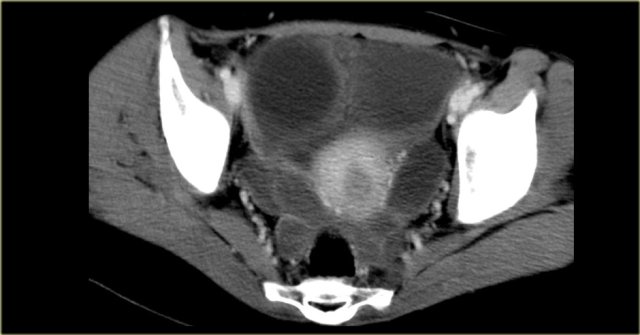

Peritoneal Inclusion Cyst

Also called Multilocular peritoneal inclusion cyst or Benign cystic mesothelioma.

This is an uncommon benign primary peritoneal tumor that has no relation with the malignant mesothelioma.

It occurs in premenopausal women with prior gynaecological surgery or infection that results in peritoneal scarring.

The hormonally active ovaries secrete fluid that becomes loculated in the pelvis.

The imaging features of a peritoneal inclusion cyst are non-specific except that it has to be located in the pelvis:

- Multicystic pelvic mass

- Enhancing septa

- Peritoneal surfaces of uterus, bladder

- May extend into upper abdomen

Peritoneal inclusion cyst (2)

When these peritoneal inclusion cysts become very large, they may extend into the upper abdomen as is seen in the case on the left.

Notice that the left ovary is encircled by the cyst (arrow).

There are also some enhancing septa.